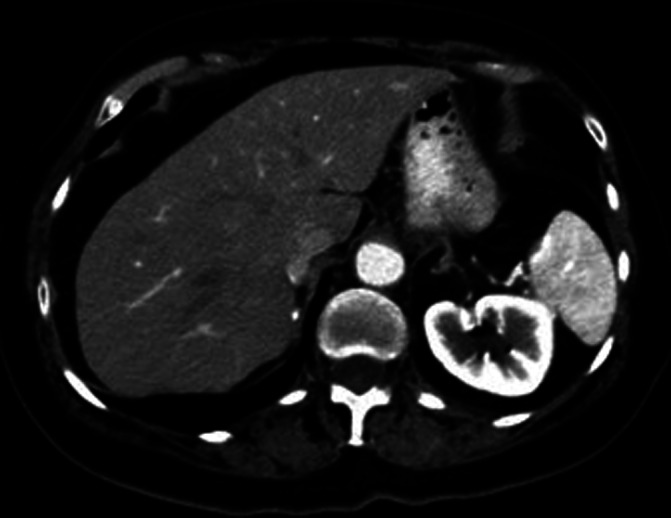

FIGURE 1.

Axial CT SCAN of the abdomen shows no evidence of splenic artery aneurysm. Images acquired February, 2021

This patient's case is interesting because of her long cumulative exposure to pazopanib. Funahashi et al. reported a case of fatal aortic dissection in a patient being treated with pazopanib and lapatinib followed by a course of sunitinib, all over the course of 5 years. 7 This highlights the importance of monitoring patients for long‐term toxicities for VEGF inhibitors. Interestingly, in Funahashi's case the patient's VEGF inhibitors were also held briefly due to intolerance issues and then their patient's arterial rupture occurred within weeks of restarting. Our patient had normal splenic artery anatomy by CT on February 10 (Figure 1), restarted her pazopanib on February 22 and then her splenic artery had developed an aneurysm and rupture all by March 5. These events do not seem to be common but perhaps closer monitoring is required within the immediate period of restarting these medications with low thresholds for ordering imaging studies.